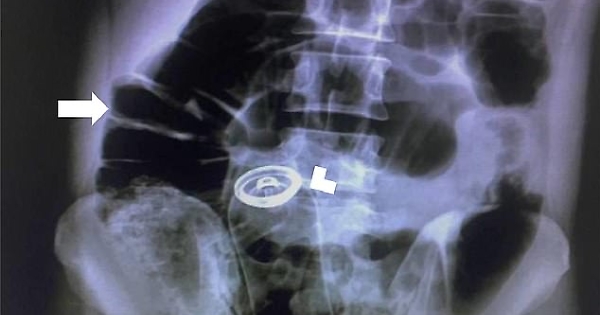

deodorant-rectum-x-ray

Un gioco erotico finito male, molto male. Un uomo ha rischiato di morire e ha dovuto essere sottoposto ad un intervento chirurgico d'urgenza, dopo che una flacone di deodorante è rimasto incastrato nel retto. L’uomo, un trentenne, ha richiesto assistenza medica "due ore dopo aver inserito un contenitore di deodorante nel suo retto", secondo quanto è stato pubblicato sul Visual Journal of Emergency Surgery.

Il paziente di nazionalità iraniana si era presentato al pronto soccorso per un "dolore addominale acuto". I raggi X hanno poi rivelato le cause. I chirurghi gli hanno praticato un'incisione sullo stomaco e gli hanno rimosso il flacone. Il paziente ha trascorso un giorno sotto osservazione prima di essere dimesso dall'ospedale.